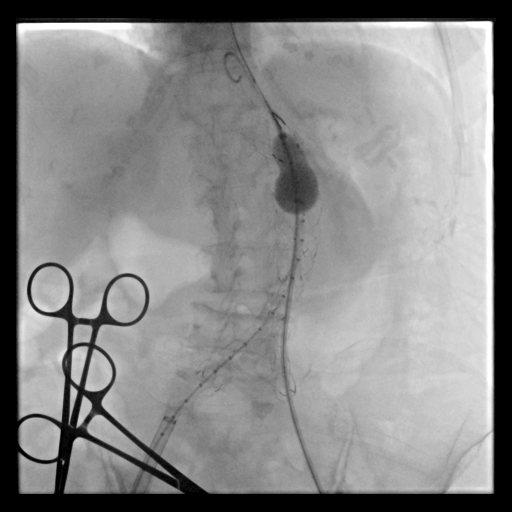

Under general anesthesia, bilateral common femoral arteries were accessed percutaneously under ultrasound guidance, and the pre-close technique with Perclose ProGlide (Abbott Vascular, USA) was applied. Angiography confirmed a large infrarenal AAA and left common iliac artery with severe stenosis (>70%) and marked tortuosity, while the right iliac was relatively straight. Guidewire advancement through the left side was difficult due to narrowing and vessel curvature.

Percutaneous transluminal angioplasty (POBA) was performed on the proximal left common iliac artery using a 10 ¡¿ 80 mm Mustang balloon (Boston Scientific, USA) inflated and showing a balloon-waist formation consistent with a tight, fibrotic lesion. After gradual dilation up to 6 atm, the waist resolved and the lumen expanded, allowing smooth wire and sheath passage. The SEAL NOVUS stent-graft system (S&G Biotech, Korea) was used, with the main body (24 ¡¿ 50 mm) introduced via the right common femoral artery. Two flared iliac limbs, 12(18) ¡¿ 100 mm on the left and 12(16) ¡¿ 80 mm on the right, were deployed in a ballerina (crossed-limb) configuration to accommodate left-sided tortuosity and prevent kinking. During contralateral limb cannulation, angiography was performed within the main body to confirm the wire course inside the graft before advancing the sheath. Completion angiography demonstrated a Type Ia endoleak, treated with proximal neck flaring using a Coda LP balloon (Cook Medical, USA) under a rapid inflation–deflation technique to optimize sealing and prevent graft migration. Final angiography showed excellent proximal seal and bilateral flow, and follow-up CTA confirmed durable aneurysm exclusion without endoleak.